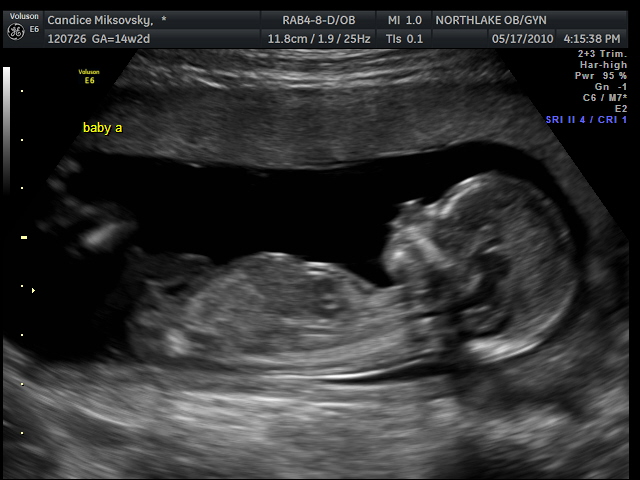

Check out the pics from today's appointment - today baby a was the boy and baby b was the girl - I guess they like to take turns!

Baby boy trying to suck his thumb!